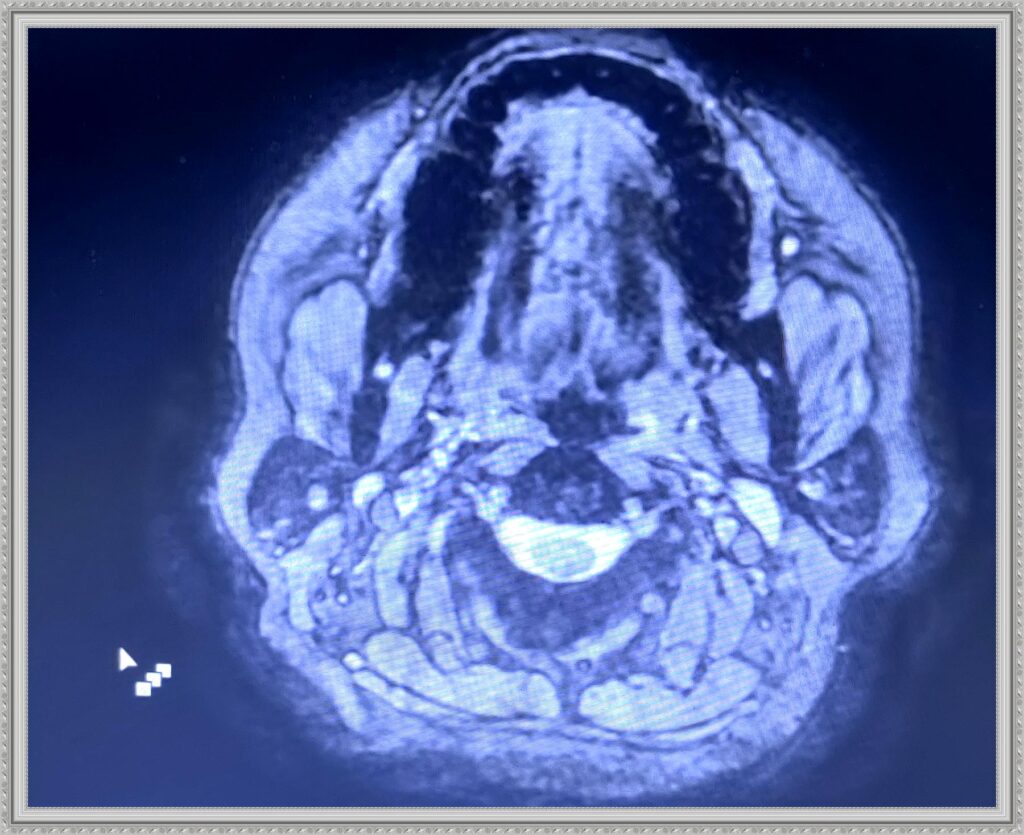

The next gallery shows me at Memorial Central Hospital in Colorado Springs after having surgery to remove my tumor and staying for a few weeks after for Physical, Speech and Occupational Therapy. The staff there was so AWESOME! I hold every one of them dear to my heart.